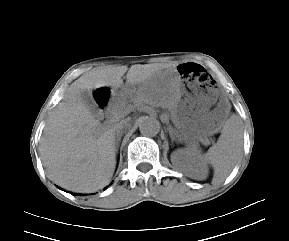

标题: CT19533:病变来源于哪?

患者,男,发现上腹部包块两月余。

病变位于肝胃间隙,实际就是位于小网膜囊(左肝下后间隙),呈轻度不均匀性强化,腹腔内及腹膜后见多发肿大淋巴结。所以我考虑肝胃间隙恶性胃肠间质瘤并淋巴结转移。

病灶强化不显著,灶周及腹膜后见多量淋巴结肿大,考虑淋巴瘤可能,其次考虑间质瘤

肝胃韧带内及腹膜后可见多发增大的淋巴结影,首先考虑转移.

考虑淋巴瘤可能。